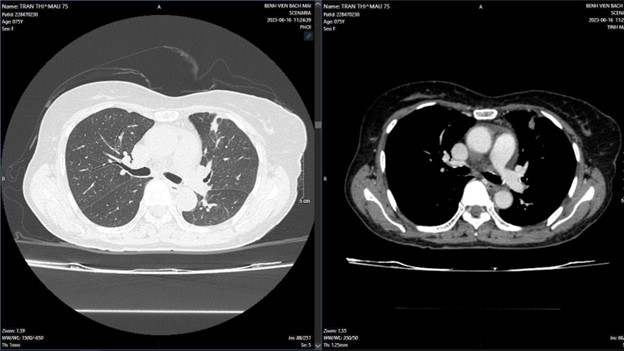

+ Sau điều trị 7 tháng:

Hình 3: Tổn thương giảm kích thước so với phim chụp sau điều trị 3 tháng, màng phổi hai bên không thấy dịch-khí